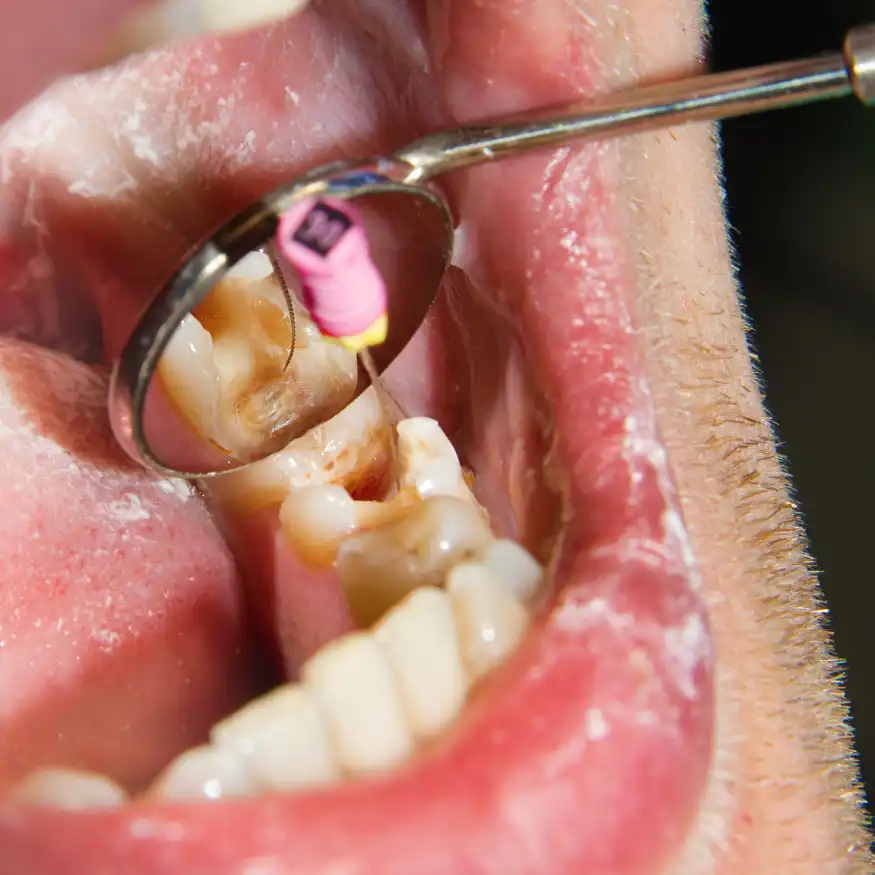

Endodoncia o Tratamiento de Conductos

La endodoncia es un procedimiento para tratar el interior del diente afectado por caries profundas o traumatismos. Este tratamiento, también conocido como “tratamiento de conductos”, se realiza para eliminar la infección en el nervio dental y conservar el diente.

Beneficios

Permite salvar el diente natural, evitando una extracción que podría desequilibrar la mordida o requerir una prótesis. Además, alivia el dolor y permite recuperar la función del diente afectado.

Proceso

Después de anestesiar el área, se realiza una apertura en el diente para extraer el tejido infectado o dañado de los conductos. Estos conductos se limpian, desinfectan y sellan con un material biocompatible. Finalmente, se coloca una corona para fortalecer el diente.